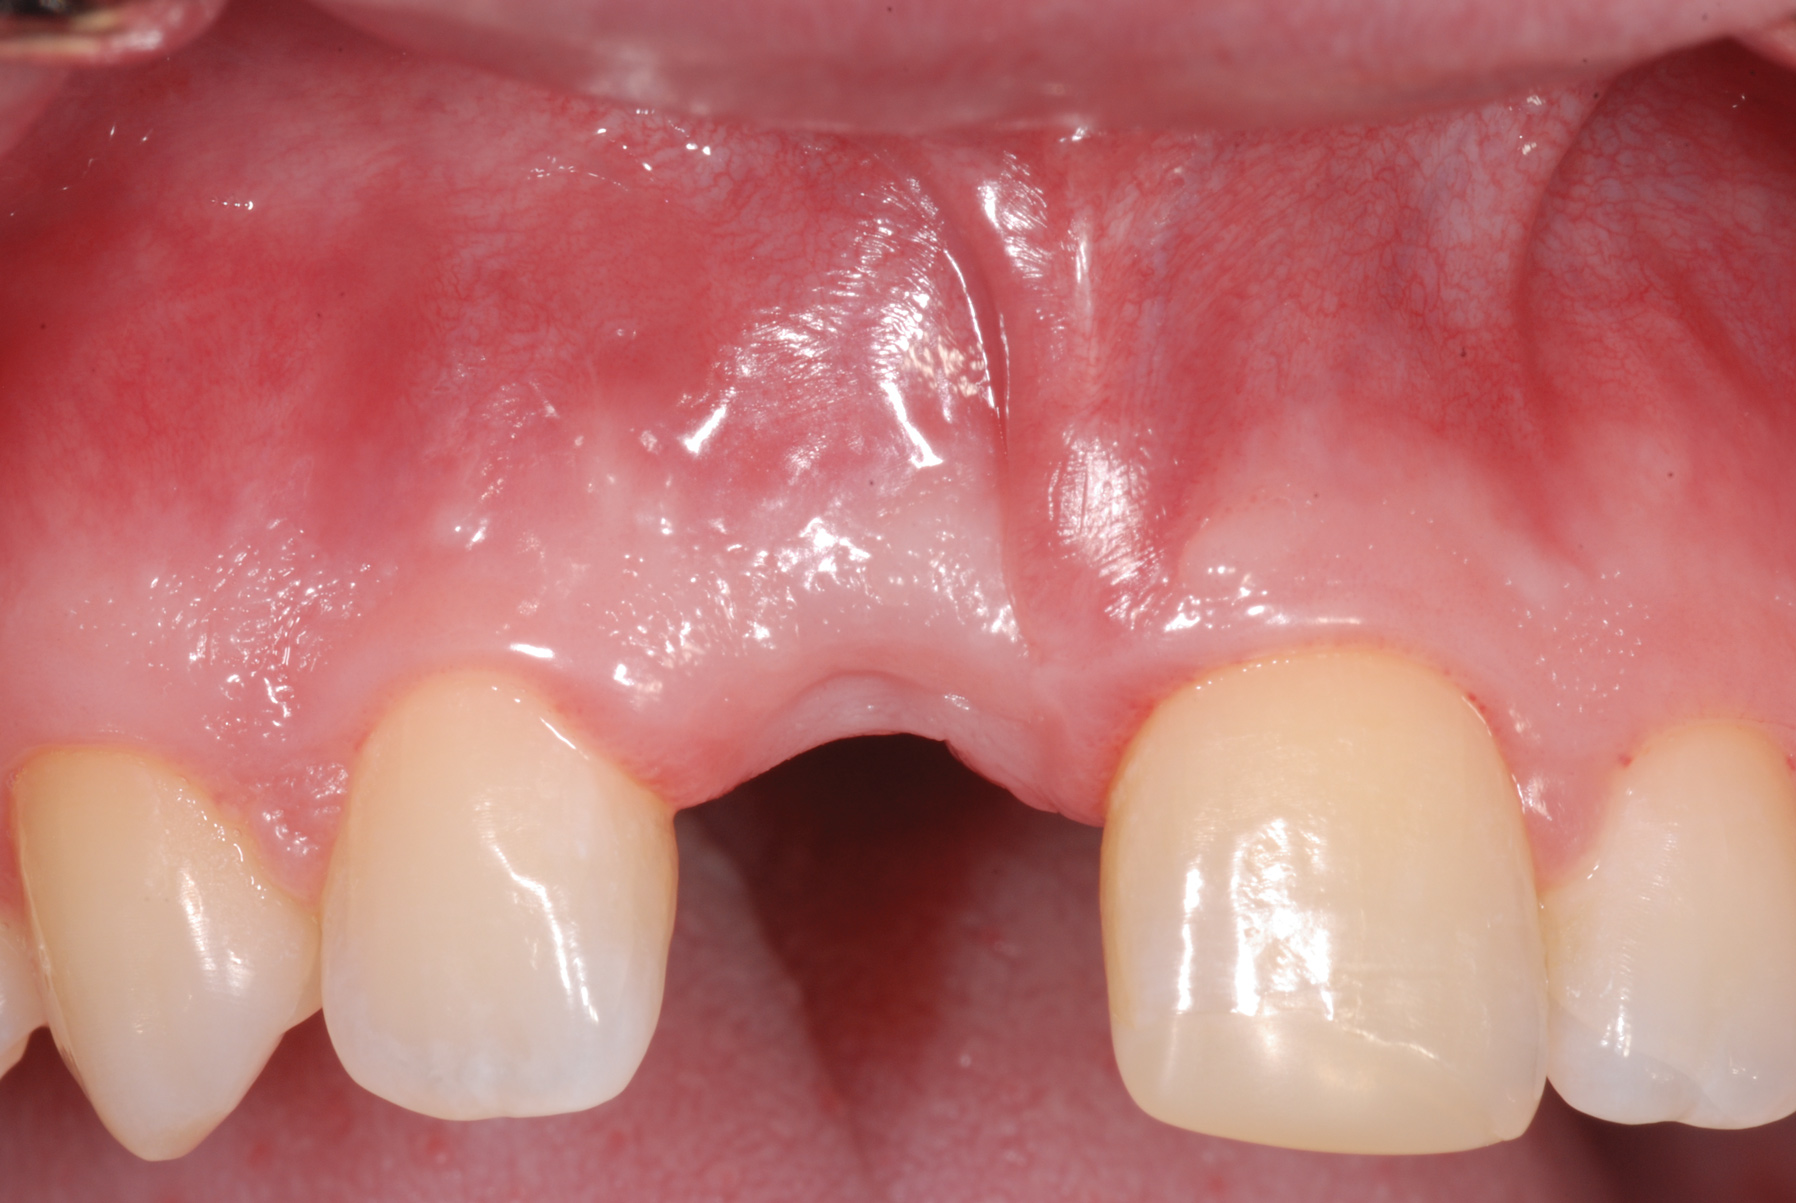

Fig 1. Age 8. Facial view of teeth Nos. 8 and 9 at initial examination.

Figure 1

Fig 5. Age 15. Facial view of the developing ridge after removal of coronal segment of tooth No. 8.

Figure 5

Fig 8. Age 19. Facial view of the ridge.

Figure 8

From age 8 to age 19, midfacial skeletal growth occurs. Without a tooth, the alveolar ridge does not fully develop vertically and the ridge loses about one-third of its labial width after the tooth is lost.16,17 In case 1, clinical photographs and radiographs were routinely obtained. When compared, photographs taken at different ages appear very similar in both the facial (Figure 5 and Figure 8) and occlusal views. The levels of the tissue in the edentulous area relative to the incisal edges of the lower anteriors were quite comparable, as were the levels of the papillae on either side of the site. The width of the alveolar ridge in the extraction sites looked much the same from occlusal views (Figure 4, Figure 6, and Figure 9).